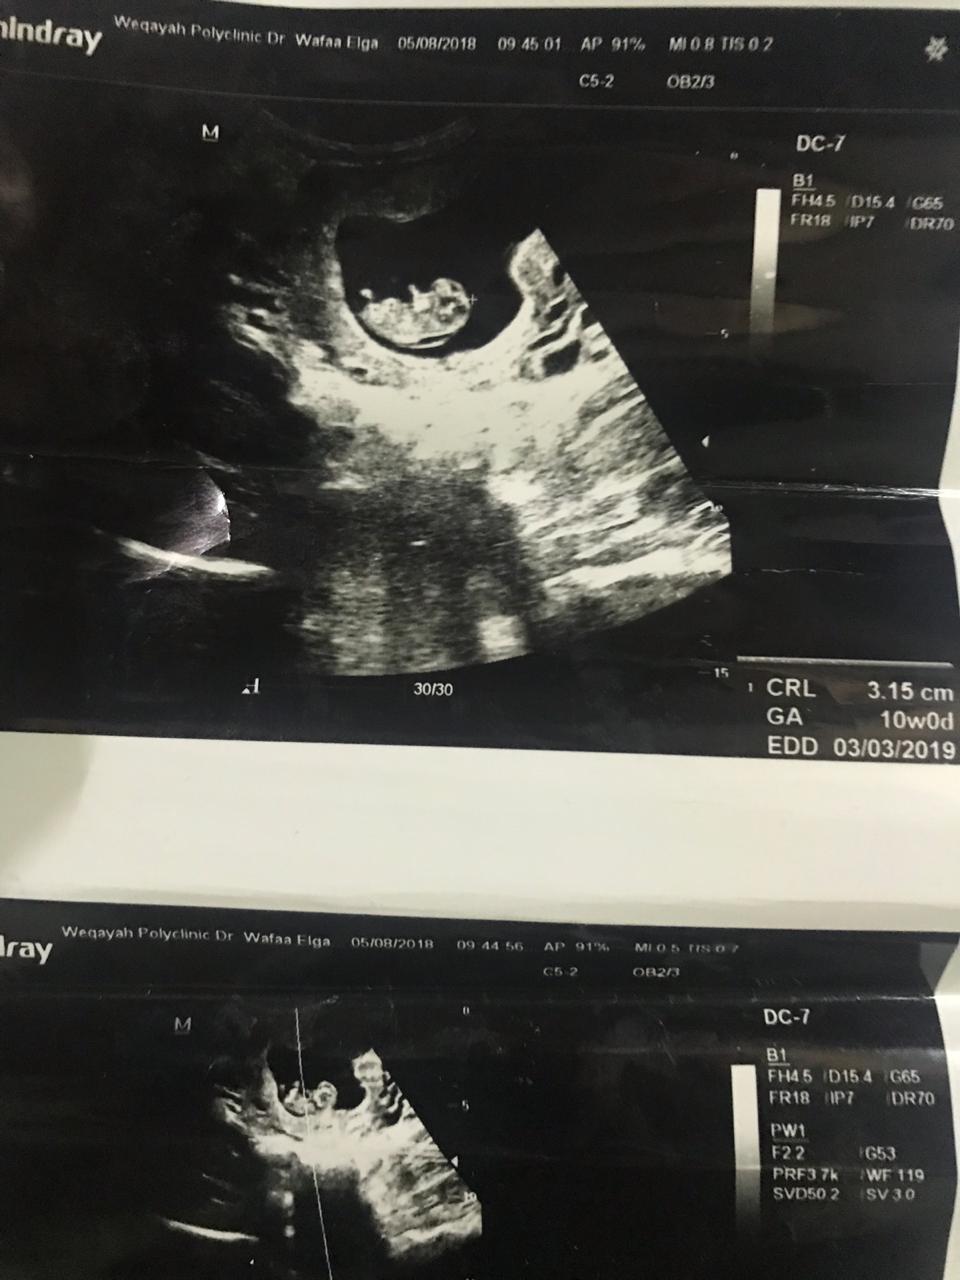

⭐- يعتمد الفحص على قياس سماكة الشفافية القفوية بإستخدام الأشعة الصوتية (السونار)

وهو عبارة عن تجمع سوائل في منطقة رقبة الجنين ويكون في فترة الحمل من 10 إلى 14 أسبوع تقريبًا

أو إذا كان طول الجنين من 36 إلى 84 ملم.

⭐- زيادة السماكة تزيد من نسبة إصابة الجنين بمشاكل صحية منها:

المتلازمات (داون,إدوارد,باتو,تيرنير),تشوه خلقي في القلب ,فتق حجابي, أو مرض جيني.

⭐- الفحص القفوي أو فحص سماكة الرقبة ليس تشخيصي بمعنى في حال كانت النتيجة غير طبيعية

تحتاج إلى فحوصات أخرى للوصول إلى التشخيص ..

وذلك عن طريق فحص الزغابات المشيمية (عينة المشيمة) أو عينة من السائل الأمنيوسي.